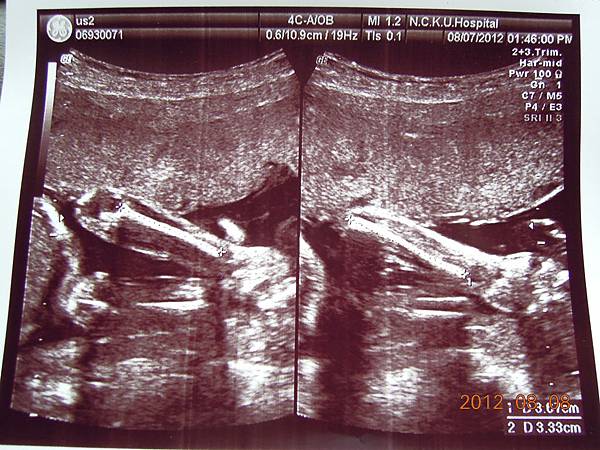

女醫師看起來超熟練,一邊照還會邊跟我解釋,這是逼逼的大腿,小腿,心臟,腎臟.....等等器官,一邊跟我媽聊天,說他生幾個....

除了比較明顯的骨頭可以看的出來,其實我們看不太懂,但是他精熟的技術很快把每個部位的大小都量測出來,我躺在床上看著上頭的螢幕,慢慢欣賞他的每張超音波照片~~

大約檢查了有四五十分鐘,也數了他的手指腳趾,看起來是沒異狀,就叫我等下把報告拿過去門診給游醫師看,還給我ㄧ堆照片,就是下面那些~~

接下來就是他的一堆檢查照片啦~~